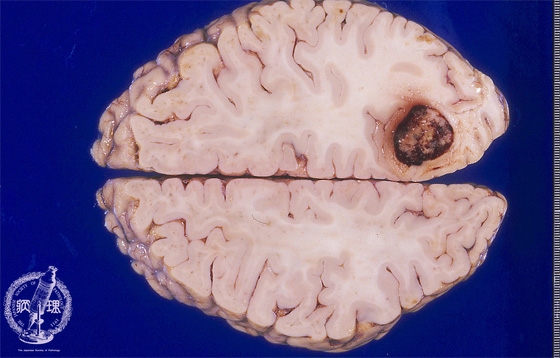

Macroscopic findings of brain metastasis from lung cancer. There was a large well-circumscribed round-shaped tumor in the right occipital lobe. Dark hemorrhagic foci were seen within the tumor and mild edema was identified around the tumor.